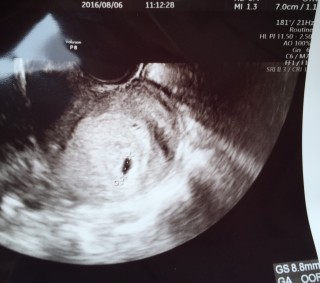

2人目です☆妊活中に科学流産があったりしましたが今回は無事子宮内にいてくれています♪実は生理予定日前にフライングでわかっていたのですがその一週間後まさかの盲腸になってしまい緊急手術。その時に胎嚢確認できました★5週くらいで9.5mmです! いろいろママを助けてくれるBabyです♪次回2週間後心拍確認できますように!